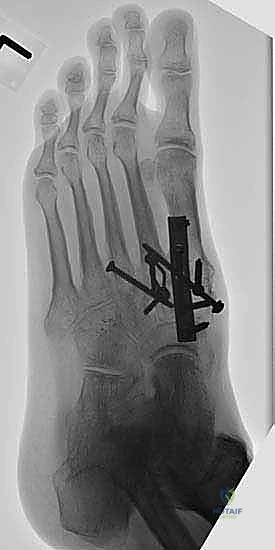

6. التثبيت الصلب (Rigid Fixation)

لضمان التحام العظام لتصبح عظمة واحدة صلبة، يجب تثبيتها بقوة هائلة حتى لا تتحرك أثناء فترة الشفاء. يتم استخدام مسامير معدنية متطورة (Screws)، أو شرائح معدنية خاصة (Plates)، أو دبابيس طبية متخصصة (Staples) مصنوعة من التيتانيوم الآمن على الجسم.

7. الإغلاق والضماد

بعد التأكد التام من وضع العظام وثباتها باستخدام جهاز الأشعة السينية داخل غرفة العمليات (C-Arm)، يتم إغلاق الشقوق الج